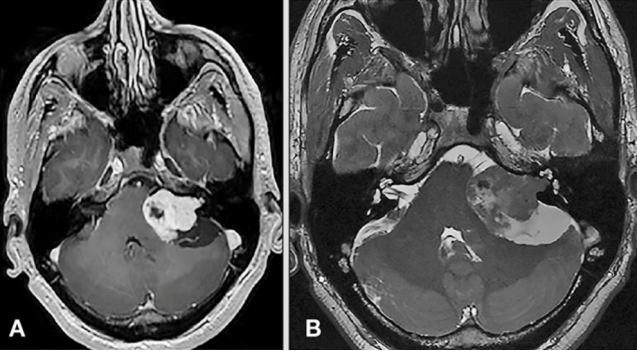

耳蜗前庭神经被一层叫做雪旺细胞的不同细胞包裹着。听神经瘤--也称为前庭神经鞘瘤--便是生长在前庭雪旺细胞的肿瘤。如果听神经瘤没有得到诊断或治疗,它可能会长得足够大,压迫脑干的重要结构,造成严重的危及生命的问题。

听神经瘤一年长多少mm?可能一年长到2cm大。患了听神经瘤的患者一般都会关注听神经瘤是恶性还是良性,一年长多少mm。INC国际神经外科医生集团旗下组织国际神经外科成员、国际神经外科联合会(WFNS)教育委员会主席、德国INI国际神经科学研究所神经外科教授(中文名:巴特朗菲)对此表示,大多数听神经瘤都是良性肿瘤,生长缓慢,需要数年才能长到足以引起症状的程度,平均生长率为2mm/年。但少数听神经瘤确实以更快的速度生长,现实中,也有患者一年肿瘤就长到2厘米大小的案例。